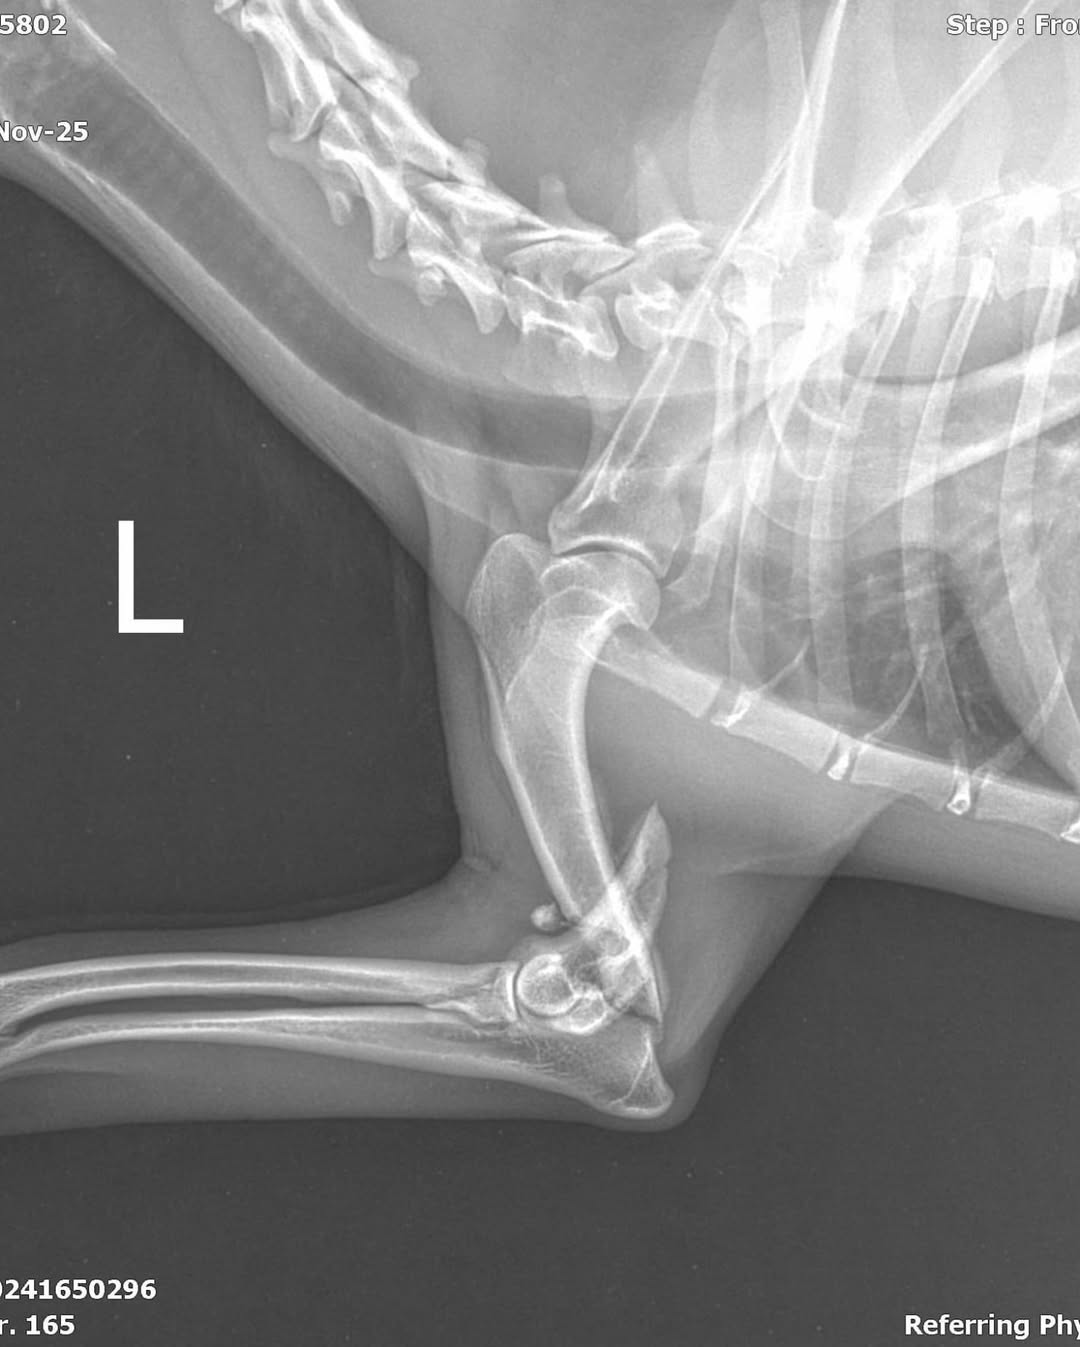

Doch ihr linkes Bein ist gebrochen. Wie es passiert ist, wissen wir nicht. Aber wir wissen eins: Ohne Operation hat sie keine Zukunft.